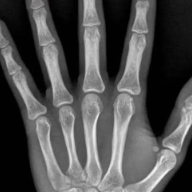

检查结果显示孩子骨骺完全闭合再无生长空间。

因为身高问题,凯凯产生了自卑心理,于是父母便带着他来到湖南中医药大学第一附属医院就诊。经过检查发现,凯凯骨龄已达18岁、骨骺闭合,成年身高定格在了157厘米。